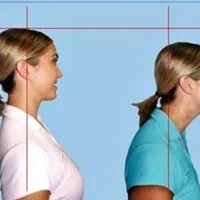

مرکز تخصصی اصلاح ناهنجاریهای اسکلتی با بیش از 15 سال تجربه درخشان زیر نظر متخصص دارای مدرک FTC از مراکز انگلیس و امارات ✅ خدمات ما: • درمان کف پای صاف و قوسدار • اصلاح پای ضربدری و پرانتزی • درمان گودی و دیسک کمر . گودی کمر و قوز • رفع درد زانو و مفاصل • درمان آرتروز و شانه یخ زده • بهبود واریس و سلولیت ویژگیهای منحصر به فرد ما: • ارائه روش اختصاصی براساس شرایط هر فرد • استفاده از متدهای نوین و علمی • پشتیبانی مستمر در طول دوره درمان • ارائه گزارش پیشرفت ماهانه شرایط پرداخت منعطف: • امکان پرداخت اقساطی • تخفیفهای ویژه سازمانی ☆ قیمت هر جلسه یکو نیم میلیون (۱/۵۰۰/۰۰۰ تومان) دوره های (۸جلسه)، (۱۶ جلسه)، (۲۴ جلسه)، (۳۰جلسه)، (۳۶ جلسه) و (۴۲ جلسه) آدرس: سبزه میدان، انتهای پیغمبریه، ساختمان هانا، مجموعه هانا ☆ برای مشاوره حضوری و تعیین وقت ؛ (نام و نام خانوادگی و شماره تماس) خود را در چت دیوار ارسال کنید و یا به شماره آگهی اس ام اس کنید. ☆ عزیزان هر سوالی داشتین از ساعت 11 صبح الی 10 شب تماس بگیرین در خدمتتون هستم. دکتر شاهمحمدی سلامتی شما، تخصص ماست